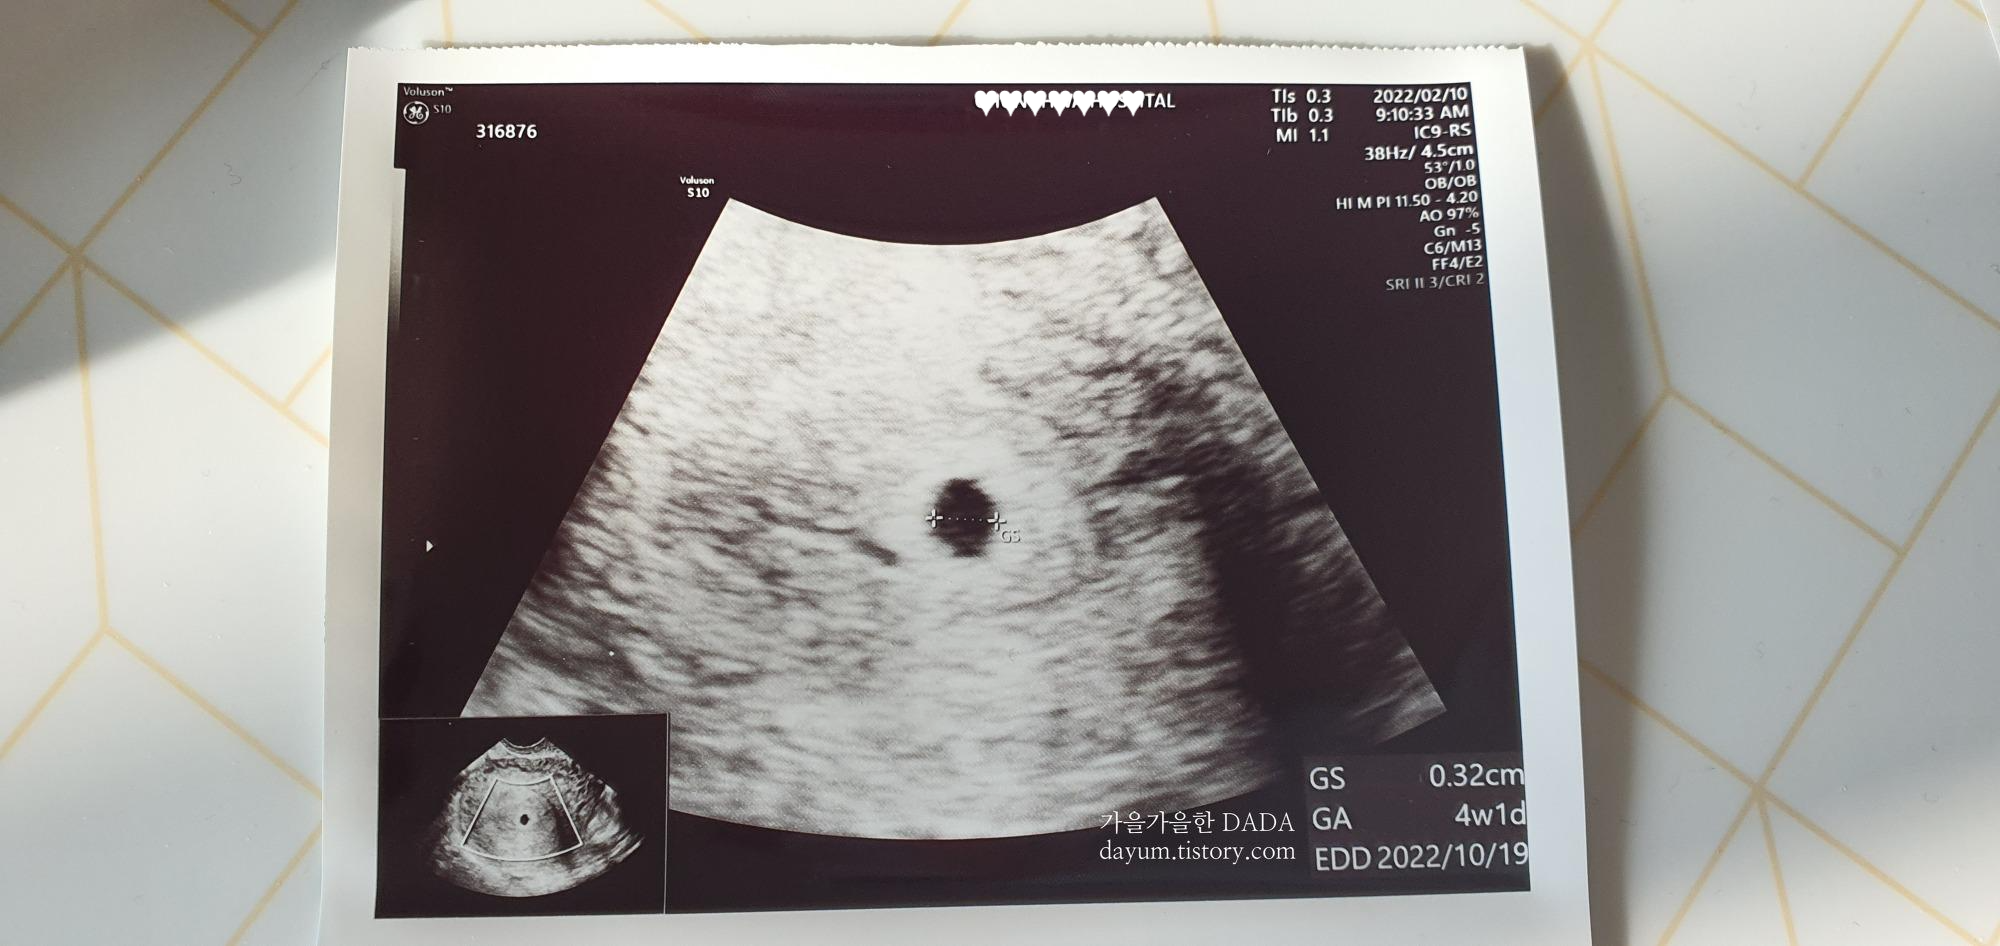

배란이 늦게 된건지 네이버 주수계산기에서는 5주차가 넘었었지만 병원에서 초음파로 봤을때는 4주1일이라고 한다.

아직 얼마 안되어서 아기집만 확인하고 집으로 돌아왔다.

초음파 보고나서는 임테기도 중단했다. 2주 후에 다시 방문예정 -